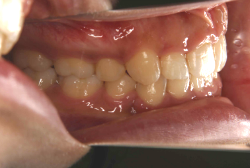

凸凹な歯並びのことを叢生といいます。矯正歯科に来院する患者様の主訴の中で、最も多いのが「配列の凸凹を真っ直ぐにしたい」というものです。歯の大きさと顎の大きさの調和がとれていないことが原因です。

凸凹を主体としたケースの場合、当院の平均治療期間は18ヶ月ですので、このケースは少し長めに経過しました。理由の一つは凸凹の程度がかなり重症だったと言うことですが、もう一つは、右下第2大臼歯が45度くらい前傾していたため、それを整直化させるために時間を要したと考えています。いずれにしても最終結果は大変よい状態と思います。

治療前は並びが乱れて見た目が悪いというのはもちろん問題ですが、歯科医学的に一番困るのは噛み合わせが悪いという点です。上下の犬歯(3番目の歯)は、上下的に離れた位置にあるため接触することができません。つまり歯としては存在していても、歯としては機能していないということです。